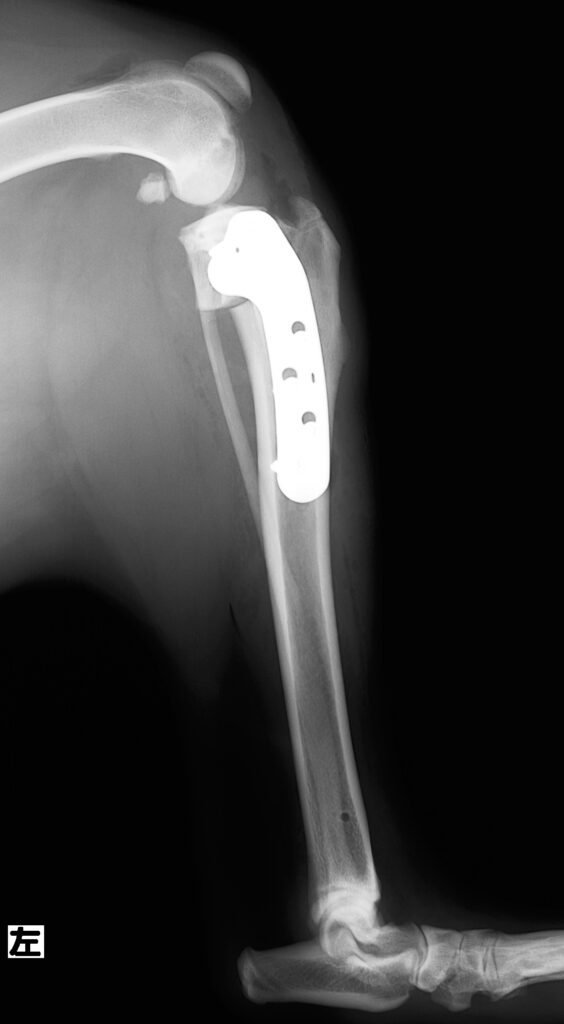

TPLO手術後の写真です。骨を切り回転させ、TPLOプレートと8本のスクリューで固定しました。

手術前と違い脛骨が後方に位置しています。

TPLOプレートは骨の大きさに合わせて非常にたくさんのサイズがある上に、左右が異なります。

今回使用したのは右のプレートです。ちなみに3kgのトイプードルさんに使用したのは左のプレードです。

大きさが全然違います!